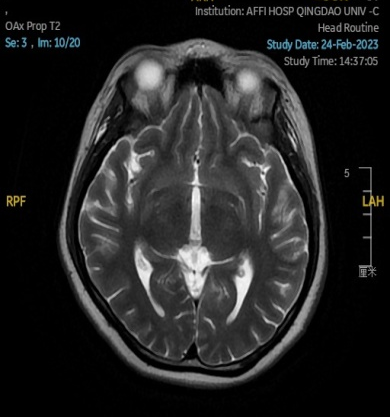

2023.02.24颅脑MR平扫示双侧基底节区及桥脑异常信号,考虑渗透性脱髓鞘综合征,见图3。

图3 2023.02.24颅脑MR成像示双侧基底节区及桥脑见对称性片样长T1长T2信号,FLAIR呈高信号。脑室、脑池、脑沟、脑裂未见明显异常。中线结构居中。